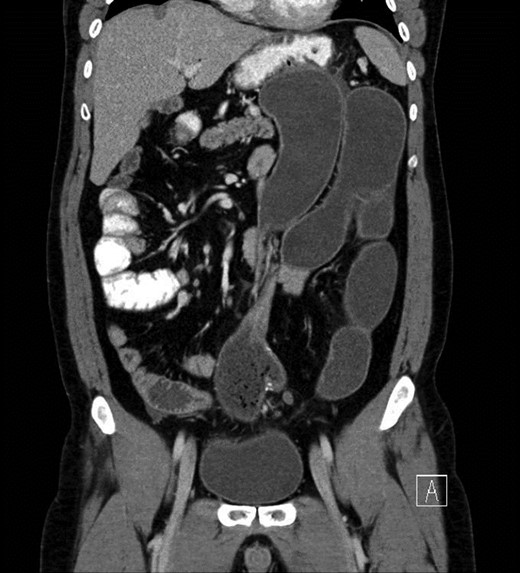

Upon presentation, he was afebrile, normotensive, and not tachycardic. On exam, his abdomen was distended with minimal epigastric tenderness and no peritoneal signs. Laboratory evaluation was notable for a mild leukocytosis of 11.1 × 103 cells/μl. Abdominal CT scan with oral contrast showed dilated loops of small bowel with swirling of the mesentery directly proximal to the pouch with concerns for a volvulus (Fig. 1).

CT concerning for volvulus of small bowel proximal to pouch with proximal distended bowel.